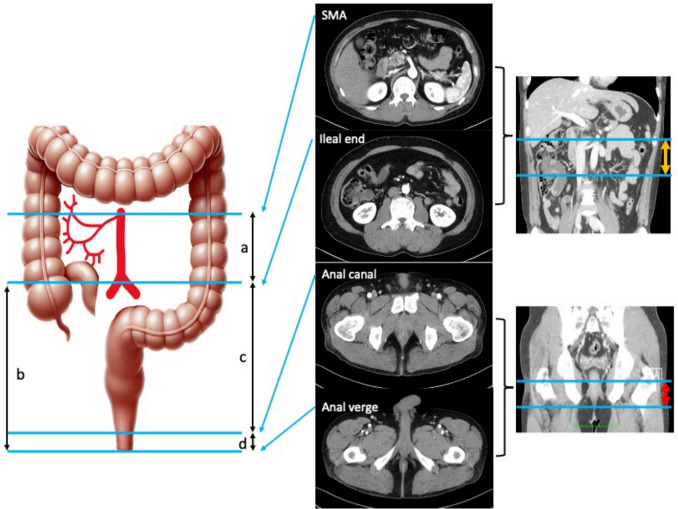

Methods: We prospectively enrolled patients with UC scheduled for two-stage restorative proctocolectomy with a preoperative plan for hand-sewn IPAA. Patients were categorized into a conversion group that required conversion to stapled IPAA intraoperatively and a non-conversion group. Preoperative visceral fat area and anatomical indicators were measured using computed tomography (CT). Logistic regression analysis was performed to identify predictors of conversion surgery.

Results: A total of 106 patients were included, with 12 (11.3%) in the conversion group. Compared with those in the non-conversion group, patients in the conversion group had significantly higher body mass index (BMI), greater visceral fat, and a longer distance between the ileal end and the anal verge (p < 0.01). Logistic regression identified visceral fat (per 10 cm2 increase: odds ratio [OR] 1.19, 95% confidence interval [CI] 1.02-1.39, p = 0.01) as a significant predictor of conversion surgery, whereas BMI was not (OR 1.03, 95% CI 0.77-1.21, p = 0.72).